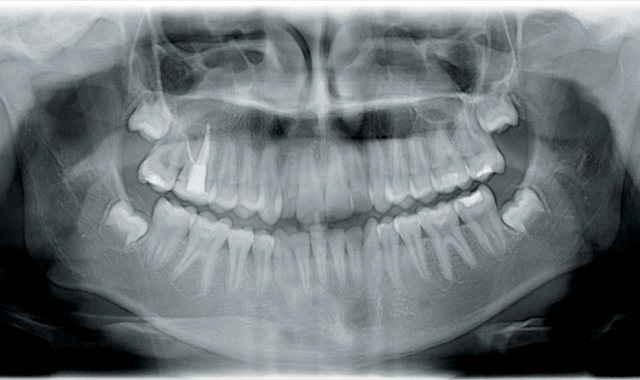

Radiographic analysis

Cephalometric analysis revealed a normodivergent, Class I skeletal pattern with well-balanced upper and lower facial heights, increased convexity, and moderately proclined and protruded maxillary and mandibular incisors were noted (Fig. 1).

Fig. 1